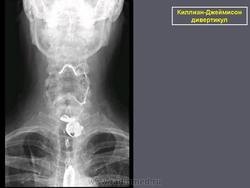

Киллиан – Джеймисон - дивертикул

Киллиан – Джеймисон - дивертикул.